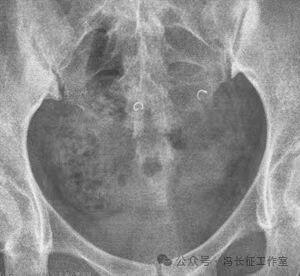

冠状位CT重建图显示宫底2侧的弹簧圈

CT三维重建显示弹簧圈都成呈C形

这就是一例单枚弹簧圈完美栓塞,明确显示栓塞单枚弹簧圈最严实。